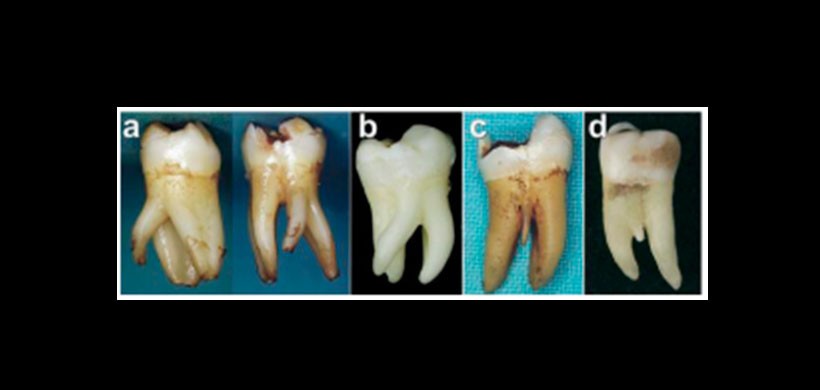

Figura 1: Fotos clínicas de primeros molares inferiores con presencia de una raíz supernumeraria a) Con dilaceración b) Con dilacercion mesial o distal c) y d) Raiz Supernumerario de una longitud menor.